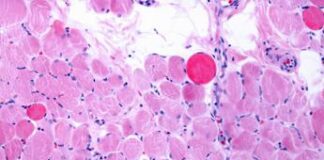

Distrofia Duchenne, via italiana per riparare e rigenerare i muscoli

(Adnkronos) - Dalla ricerca italiana una nuova strategia per favorire la riparazione e la rigenerazione dei muscoli nei malati di distrofia di Duchenne. La...